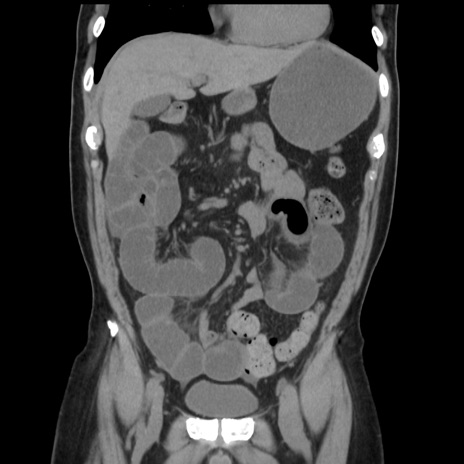

症例16(冠状断像)

【症例】 70歳代男性

【主訴】 腹痛、嘔吐

【現病歴】 約1ヶ月前より間欠的に腹痛と嘔吐あり、当院消化器内科を受診したところCTで多発する肝臓のLDAを指摘され、精査中であった。以降は消化器症状は安定していたが、2日前より嘔気と腹痛があり、同日より排便・排ガスが消失した。改善認めず、 本日、救急外来を受診した。

【既往歴】 大腸ポリープ切除後。

【身体所見】意識清明・会話良好、BT 36.3℃、BP 127/80mmHg、 P 80bpm、腹部:膨満あり、平坦・軟、上腹部正中および下腹部正中に圧痛あり、反跳痛なし、筋性防御なし。

【データ】WBC 7200、CRP 0.77